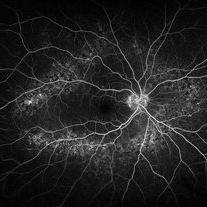

Central Serous Chorioretinopathy

Central Serous Chorioretinopathy

Jan 25 2022 by Olivia Rainey

Late phase widefield fluorescein angiography of a 60-year-old male with Central Serous Chorioretinopathy. Chronic history of CSR followed with observation without treatment prior to presenting at our office. The physician noted significant findings on exam and imaging with multifocal areas of inactive and active changes OD. FA shows superotemporal macular leakage, subtle inferonasal macular leakage and staining as well as multifocal hypercyanescence on ICG. Fortunately foveal sparing and thus observation is recommended at this time OD.

Photographer: Olivia Rainey, OCT-C, COA

Imaging device: Heidelberg Spectralis

Condition/keywords: 55-degrees, central serous chorioretinopathy (CSCR), central serous retinopathy (CSR), chronic central serous chorioretinopathy (CSCR), fluorescein angiogram (FA), fluorescein leakage, heidelberg spectralis, indocyanine green (ICG) angiography, late phase